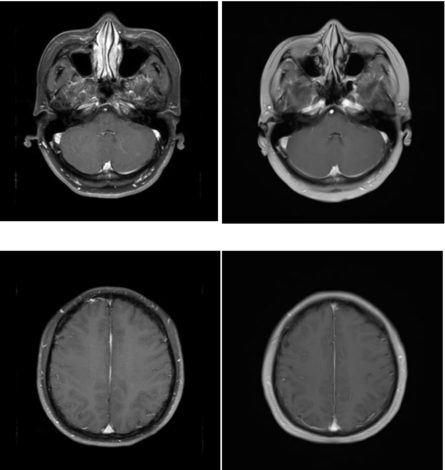

• 乳腺MR(2023年10月9日):右乳中央区及外下象限见两个不规则肿块,右侧乳头及乳晕与肿块分界不清,考虑恶性,请结合临床综合分析(BI-RADS6);右侧腋窝见肿大淋巴结;双侧乳腺内见散在结节状显著强化灶,性质待定(BI-RADS 3)。

图 2023年10月9日乳腺MR